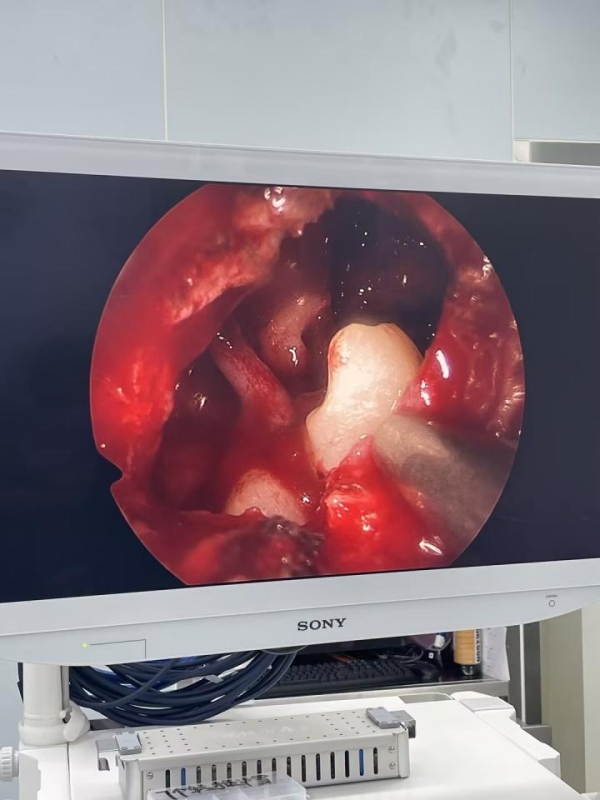

近日,40岁的张先生因面部肿胀到泰康同济(武汉)医院就诊,却在拍片时意外发现自己原本应该长在口腔里的两颗牙齿,竟然跑到了鼻窦里。医生通过微创手术,帮他从鼻窦里"拔"了牙。目前张先生恢复情况良好,不日将出院。

耳鼻咽喉科王美荣主任在详细询问病史及现场看诊后,结合CT检查结果,判断是张先生的左侧鼻窦长了两颗异位牙,由此引发的牙源性囊肿破坏了周围结构,进而引起了面部红肿压痛。